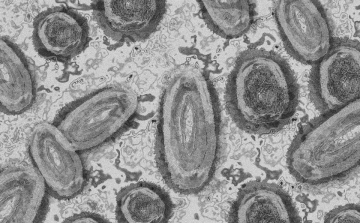

Meghaladta a 13 ezret a majomhimlő-fertőzöttek száma az Egyesült Államokban

Meghaladta a 13 ezret a majomhimlő-fertőzöttek száma az Egyesült Államokban, a legtöbb esetet Kaliforniában és New York államban regisztrálták.

Tovább nőtt a majomhimlő-fertőzöttek száma Magyarországon

Újabb kilenc, 23-50 éves férfinél igazolták a majomhimlő-fertőzést Magyarországon, ezzel 42-re nőtt a fertőzöttek száma - közölte a Nemzeti Népegészségügyi Központ (NNK) csütörtökön az MTI-vel.

Tovább nőtt a majomhimlő magyar fertőzöttjeinek száma

Újabb hat embernél diagnosztizálták a majomhimlő vírusát, így harmincra emelkedett az igazolt fertőzöttek száma Magyarországon - közölte a Nemzeti Népegészségügyi Központ (NNK) pénteken az MTI-vel.

Újabb hét magyarnál igazolták a majomhimlőt

Újabb hét embernél igazolták a majomhimlőfertőzést a Nemzeti Népegészségügyi Központ (NNK) veszélyes kórokozókkal foglalkozó laboratóriumában; ezzel 19-re nőtt az igazolt majomhimlő fertőzöttek száma Magyarországon